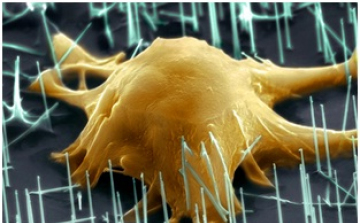

A gyomorrák kialakulásának négy mechanizmusát azonosították

2013. Január 26. 05:00, szombat | Belföld

A melanóma növekedését \'ösztönző\' génmutációkat fedeztek fel